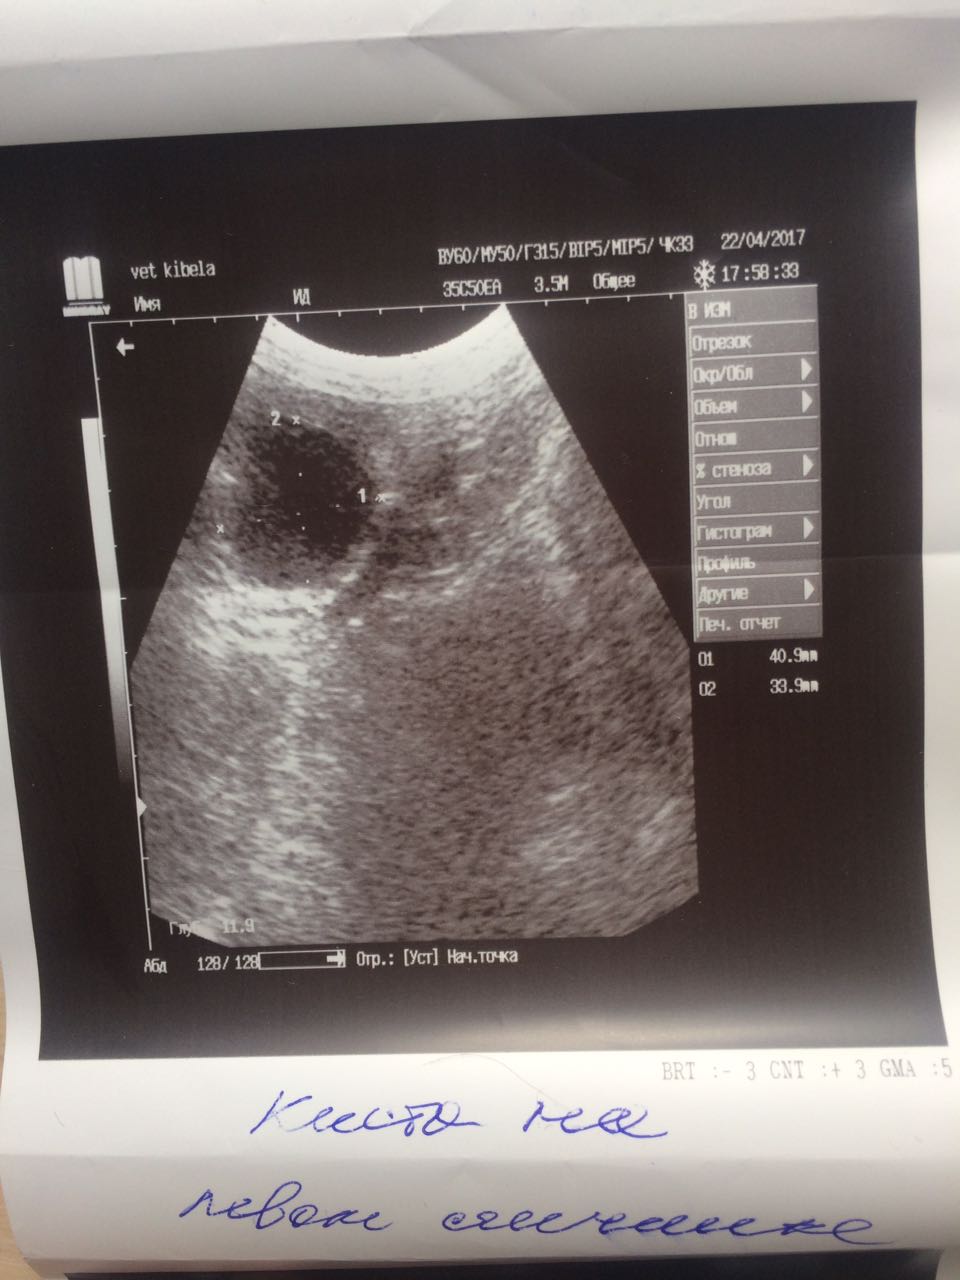

Теперь немного о том что мы нашли на обследование.Не смотря на мои призрачные надежды на доброкачественность образований ,у Лады рак молочной железы. Предположительно похоже на карциному.Конечно хирург сквозь кожу не может разглядеть наверняка ,но полагаясь на опыт может предположить.Из УЗИ мы выяснили ,что пока метастазов в печени,в других органах у нас нет.Есть достаточно большая киста на яичнике и возрастные изменения в почках.